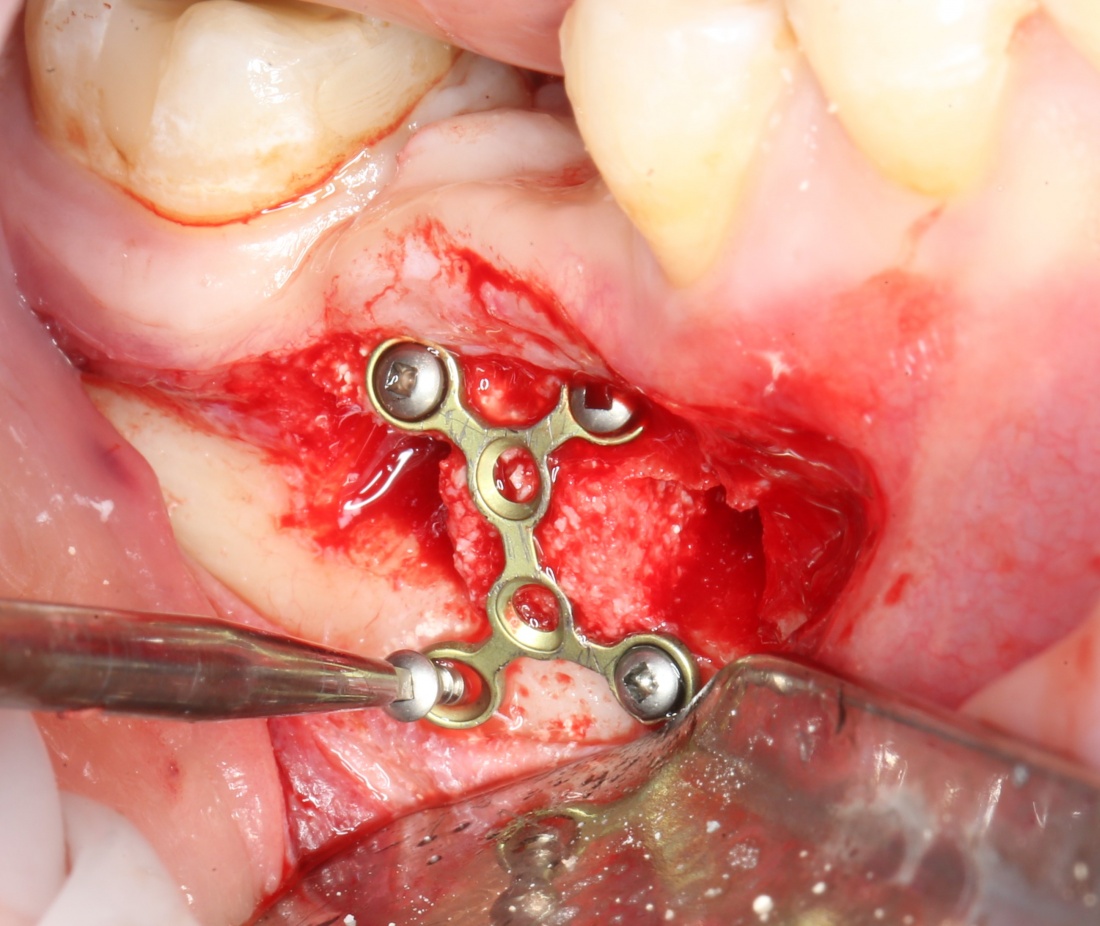

— минипластины. Их выпускается огромное количество. Мы используем, в основном, X- и Н-образные минипластины наименьших размеров — с ними легче работать, они легко адаптируются, но есть и минус — иногда гнутся под нагрузкой.

Мы особо не паримся с металлом, предпочитая ритм-энд-блюз или джаз, но если приходится, то нас вполне устраивает отечественный производитель «Коррозия металла» КОНМЕТ:

При горизонтальной остеотомии, на мой взгляд, удобнее использовать минипластины. Как я уже отмечал выше, в практике мы используем X- и H-образные минипластины под винты размером 0.9х4мм. Количество металла в разных условиях может быть разным — всё зависит от того, на каком этапе достигается полная неподвижность перемещенного костного фрагмента.